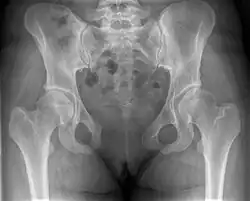

Внешний вид лобкового симфиза таза -

Левая тазовая кость и лобковый симфиз (в разрезе) -